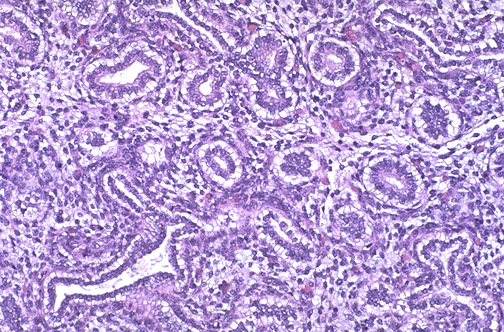

In the first part of the second trimester, the fetal lung is in the glandular phase (tubular phase) of development. There are only primitive rounded bronchioles, and no alveoli have yet formed.